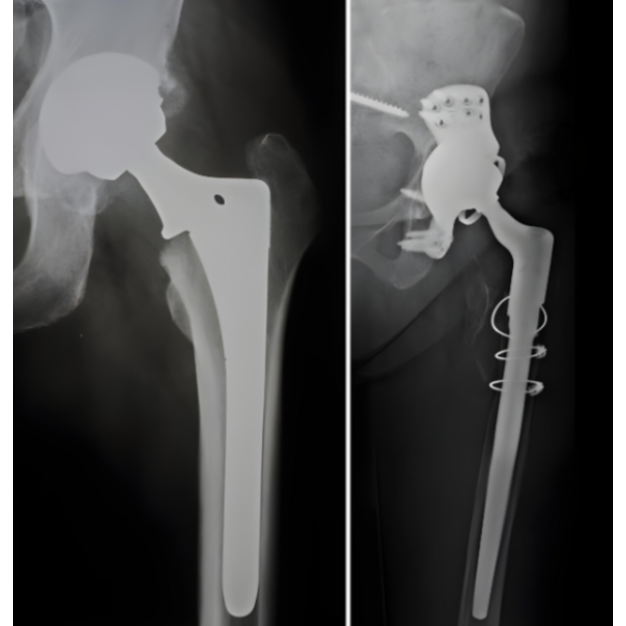

Severe hip pain can limit movement and independence. Kulkarni Orthopaedic Center Bangalore offers advanced primary hip replacement surgery to restore comfort, mobility, and confidence. The procedure replaces the damaged hip joint with a prosthetic implant, allowing smoother, pain-free motion and better joint stability.

Primary hip replacement is often recommended for patients with arthritis, fractures, or joint degeneration. The experienced team ensures precise alignment of the implant to match each patient’s anatomy, ensuring optimal balance and movement. Modern surgical techniques and durable implants make recovery quicker and more comfortable.